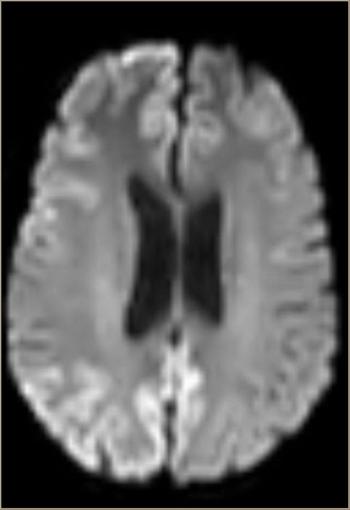

Creutzfeldt-Jacob disease should be considered in the setting of a rapidly progressive dementia with psychiatric symptoms, ataxia, mutism, myoclonus, and pyramidal or extrapyramidal signs.